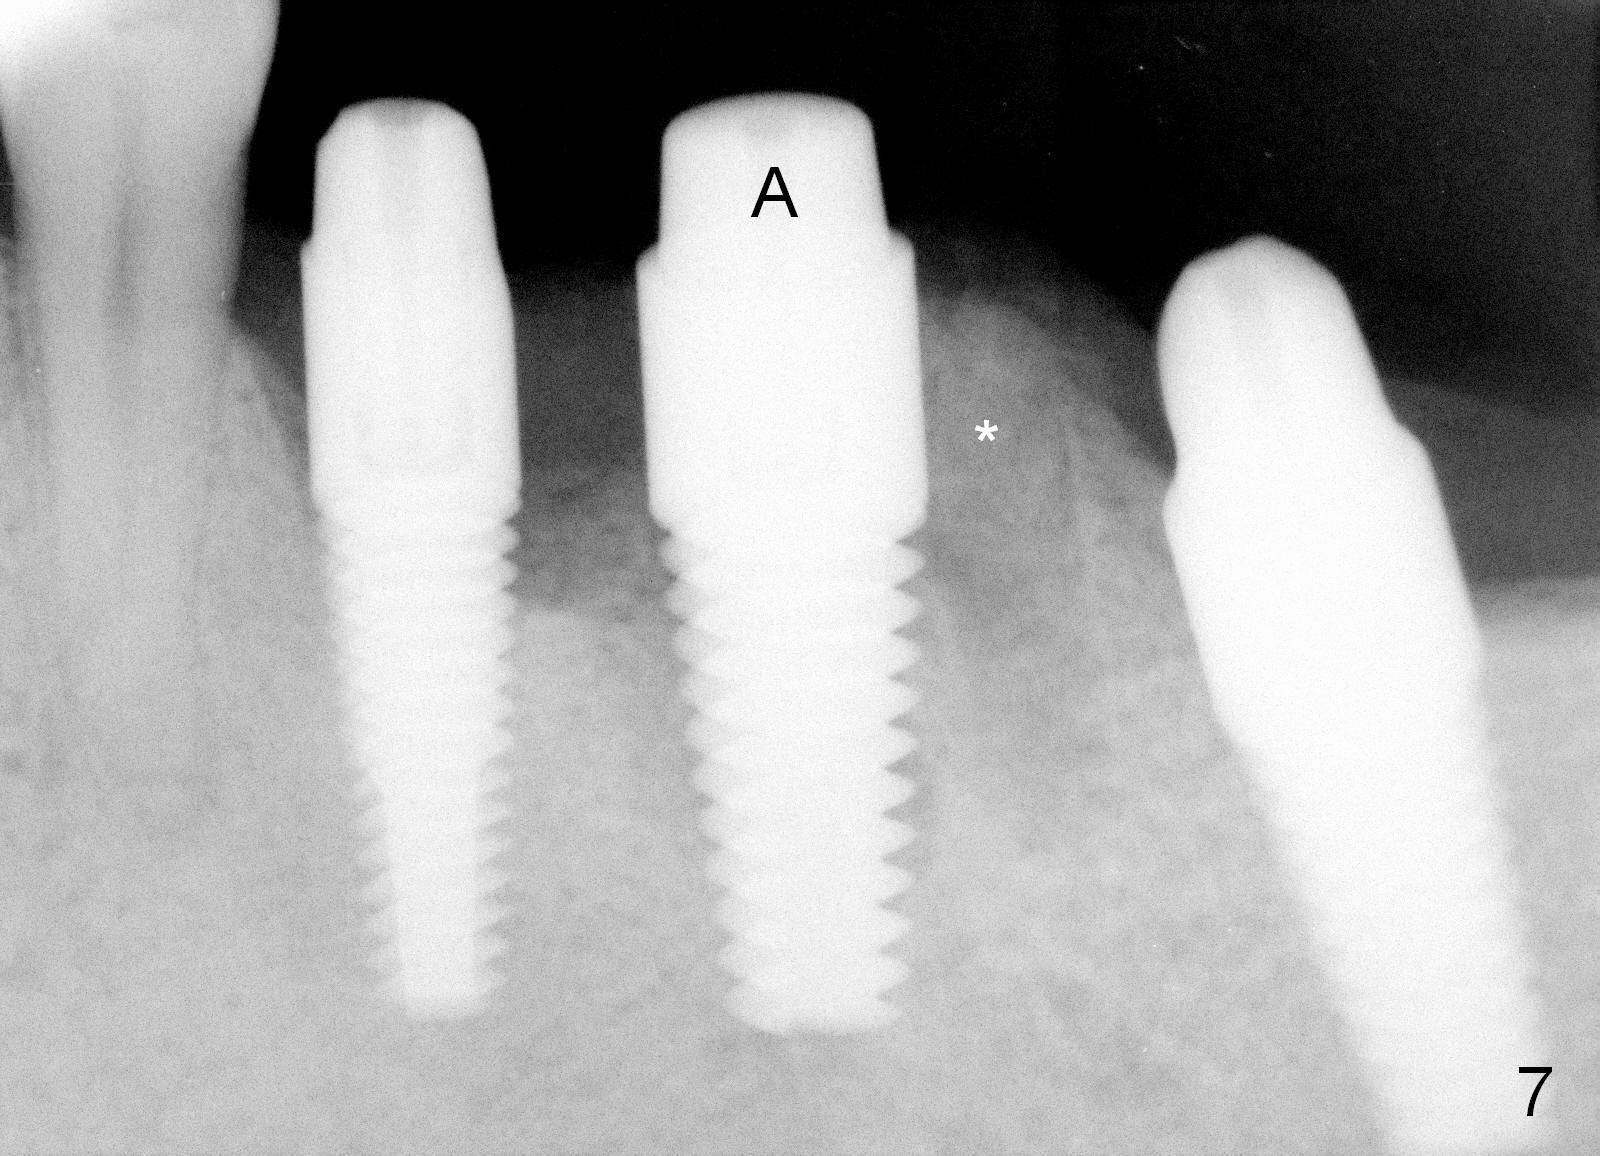

After placing the implant a little deeper, bone graft is placed in the distal socket (Fig.7 *). Three abutments are placed (A) in the 3 adjacent implants. Perio dressing is applied around these abutments to close the remaining gaps of #19 sockets.